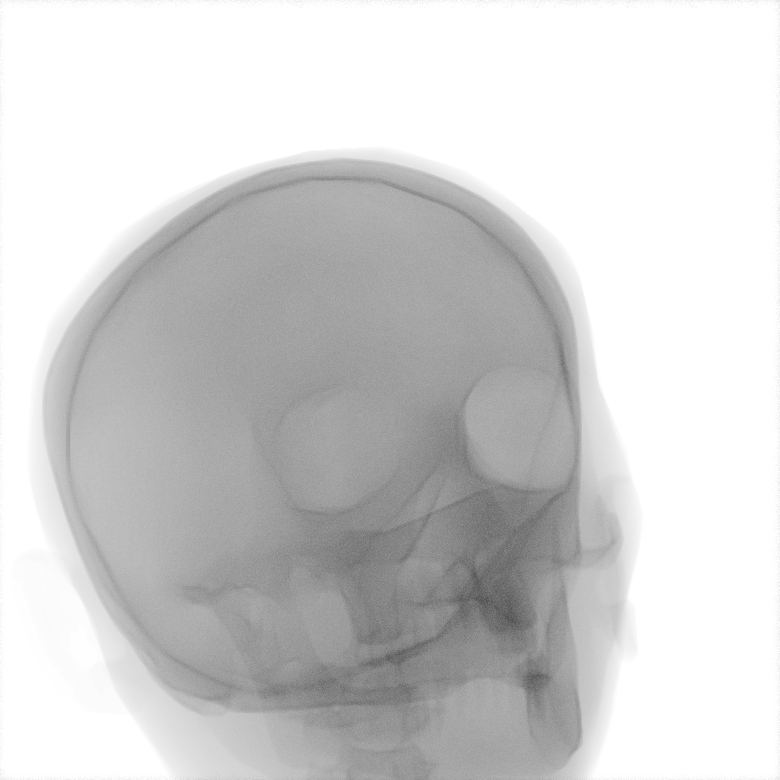

Refer to caption

Figure 1: Overview of MedShift inference. A source image x1x_{1} is first encoded into a domain-agnostic latent representation zτz_{\tau}. This latent lies near a shared manifold across all domains. Then, translation is performed by forward-time sampling conditioned on the target domain label to obtain the translated image x^1\hat{x}_{1}.

During inference, a source image, such as a simulated X-ray (class S), is first encoded into a domain-agnostic latent representation via time integration. Starting from the observed image x1x_{1}, we integrate backward from t=1t=1 to an intermediate time τ(0,1)\tau\in(0,1) under the source domain condition c=Sc=S, yielding the latent representation zτz_{\tau}:

zτ=x1τ1vθ(xt,c=S,t)dt.z_{\tau}=x_{1}-\int_{\tau}^{1}v_{\theta}(x_{t},c=S,t)\,dt. (1)

This intermediate state lies in a shared latent manifold that is approximately aligned across all domains, as shown in Section B. To generate the translated image in a target domain, e.g., a real X-ray at high dose, we then integrate forward from τ\tau to 11, this time conditioning the target domain c=Rc=R:

x^1=zτ+τ1vθ(xt,c=R,t)dt.\hat{x}_{1}=z_{\tau}+\int_{\tau}^{1}v_{\theta}(x_{t},c=R,t)\,dt. (2)

This two-stage process, consisting of encoding and translation, enables faithful domain transfer while preserving essential anatomical content. Figure 1 illustrates this conditional transport mechanism between domains.